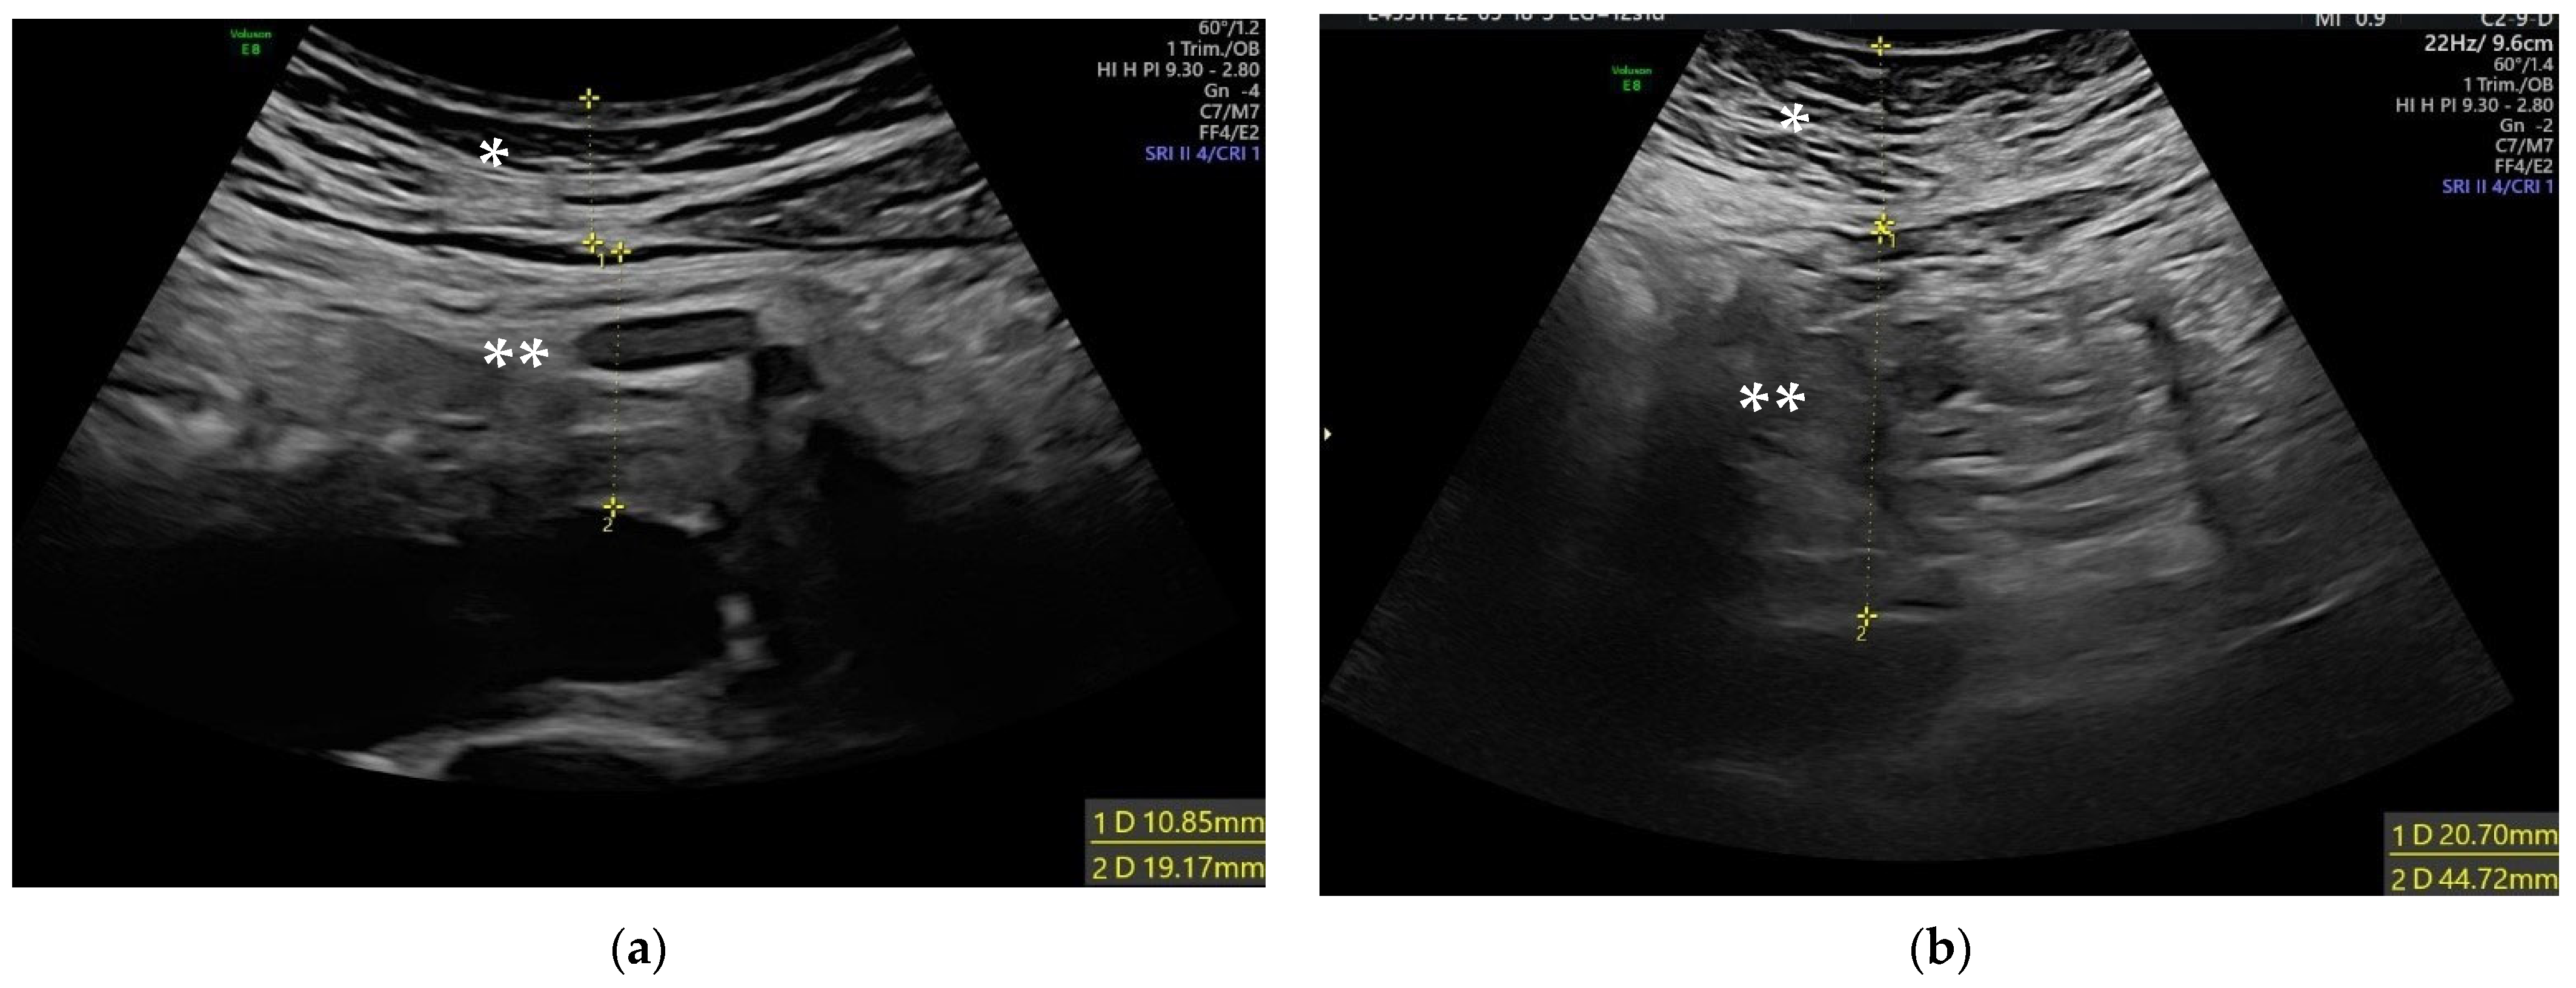

2.2. Ultrasound Measurements

| Ultrasound Parameters | |||

| SFT (mm) | 17.1 (13.1–21.4) | 18.9 (14.3–24.2) | p = 0.03 * |

| VFT (mm) | 26.5 (19.5–35.9) | 30 (23.4–45) | p = 0.001 * |